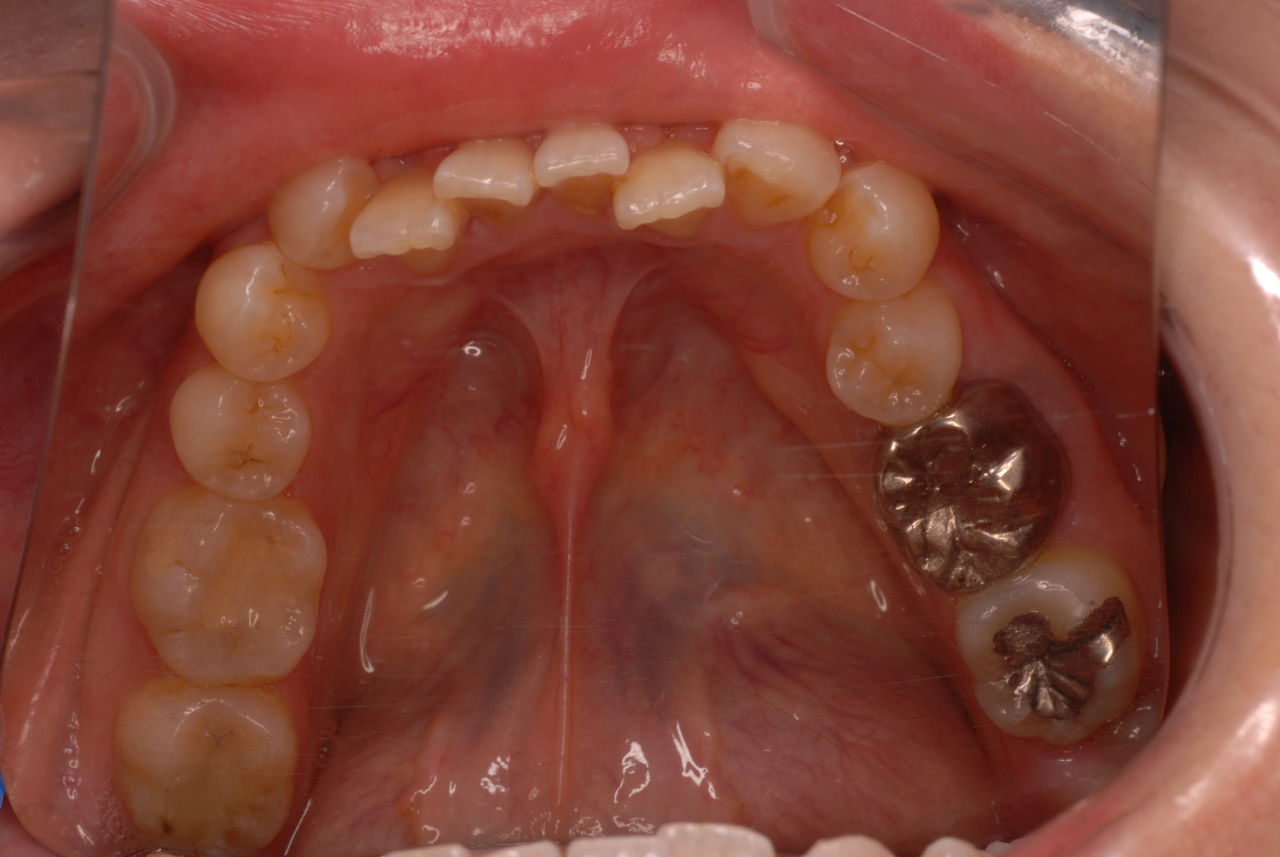

写真左下の親知らずが痛くなり抜歯しました。その後歯茎を除去して虫歯を露出させる処置を二回ほどしています。

レントゲンでは小さいですが、こう言う虫歯が一番怖いのです。

治療の成功率は極めて悪くすぐ再発しやすいのです。